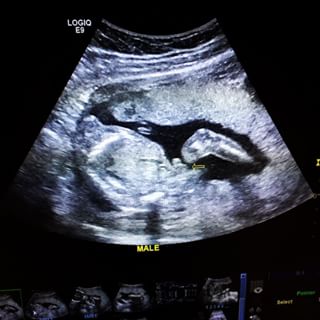

เขตต์ ฐานทัพ แนท เปรมิการ์ เผยภาพอัลตราซาวด์ 19.2 สัปดาห์ ได้ลูกชายครับผม ตั้งชื่อแสนน่ารักรอ น้องดีจ้า

หลังหนุ่ม เขตต์ ฐานทัพ ออกมาประกาศข่าวดีว่าภรรยาสาว แนท เปรมิการ์ ตั้งครรภ์เตรียมเป็นว่าที่คุณพ่อคุณแม่มือใหม่แล้ว โดยเรียกชื่อลูกในท้องน่ารัก ๆ ว่า น้องดีจ้า ล่าสุด (28 กรกฎาคม 2558) เขตต์ ได้โพสต์ภาพขณะพาภรรยาสาวที่ตั้งครรภ์ได้ 19.2 สัปดาห์ ไปทำอัลตราซาวด์ ก่อนจะพบข่าวดีว่าทั้งคู่ได้ลูกชาย

โดย เขตต์ ฐานทัพ ได้โพสต์ข้อความลงในอินสตาแกรมว่า "28/7/58 มาตรวจน้ำตาลแม่แม่ เจอของแถมมมม !!! จู่ ! จู๋ ! จู๋ ! โผล่ จร้าาาา 555 ^^ #djaaa️ 19.2 week"

ทางด้านภรรยาสาว แนท เปรมิการ์ ก็ได้โพสต์ข้อความว่า "กา กา กา...กาจู๋ โผล่ !!!! 5555 เด็กชายดีจ้า มาแว้วฮ๊าฟฟฟฟฟ #djaaa️ #19.2"